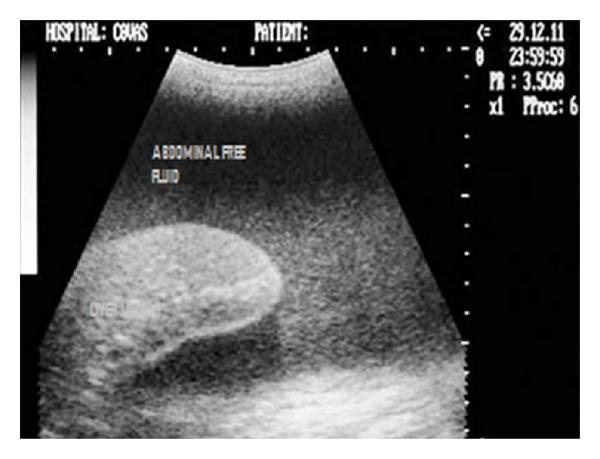

Hepatic disease is often treatable and has a predictable prognosis when a definitive diagnosis is made. The aim of clinicopathological evaluation of hepatobiliary affections is to identify and characterize hepatic damage and dysfunction, identify possible primary causes of secondary liver disease, differentiate causes of icterus, evaluate potential anaesthetic risks, assess prognosis and response to xenobiotics, and monitor response to therapy. This paper describes the different diagnostic methods and imaging techniques employed in diagnosis of hepatobiliary affections in dogs. Besides reviewing the significant clinical manifestations and imaging structural abnormalities in diagnostic approach to different hepatic affections, it also depicts radiographic, ultrasonographic, and wherever applicable, the laparoscopic characterization of different hepatic affections and target lesions encountered in clinical cases presented in the Teaching Veterinary Clinical Complex, COVAS, Palampur in the year 2007-2008.

肝病通常是可治疗的,一旦做出明确诊断,其预后是可预测的。肝胆疾病临床病理评估的目的是识别和描述肝损伤及功能障碍,确定继发性肝病可能的主要病因,鉴别黄疸的病因,评估潜在的麻醉风险,评估预后及对外源化学物质的反应,并监测治疗反应。本文描述了用于诊断犬肝胆疾病的不同诊断方法和成像技术。除了回顾不同肝病诊断方法中的重要临床表现和成像结构异常外,还描述了2007 - 2008年在帕兰普尔兽医临床综合教学中心(COVAS)出现的临床病例中不同肝病及目标病变的放射学、超声学特征,以及在适用情况下的腹腔镜特征。